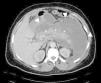

Case reportThis is a 45-year-old African American male presenting with a 2-week history of abdominal pain, anorexia, and pain during intercourse. His history was significant for an episode of severe alcohol related pancreatitis two months prior complicated with multiorgan failure and a prolonged hospitalization. There was no mention of dysuria, urethral discharge, testicular pain, history of pelvic surgery or prior similar complains in the past. Physical exam was significant for normal vital signs, and diffusely tender distended abdomen without organomegaly. A 2 x 4cm tender non-reducible mass was palpated in the left inguinal region. Pertinent laboratory results included mild leukocytosis, normal pancreatic enzymes and normal transaminases. Urine analysis was unremarkable. Abdominal CT with contrast revealed a large septated fluid collection of approximately 30cm in diameter, extending from the lesser sac to the left side of the pelvis into the left inguinal canal and scrotum. The collection was compressing against the stomach, duodenum, spleen, but there was no radiological signs of obstruction (Fig. 1). It dissected following the path of the left psoas muscle down to the pelvis (Fig. 2). At the level of the inguinal canal, it compressed against perineal structures including the base of the penis (Fig. 3). Communication of the retroperitoneal and inguinal collection was determined by visualization of the continuum through the different tomographic cuts. At all levels the collection presented with Hounsfield units ranging from five to 15, corresponding to the attenuation coefficient of cystic fluid. Percutaneous drainage was precluded due to the multiloculated nature of the pseudocyst. Considering persistence of abdominal pain and inability to advance diet, the patient underwent laparoscopic surgical drainage, and 3.5 liters of non-purulent fluid was retrieved. Seven days after the surgery, the patient presented with tachycardia, fevers, worsening abdominal pain and increased output from surgical drains. Cultures confirmed peritonitis with Pseudomona aeruginosa and methicillin resistant Staphylococcus aureus. The patient required a total of five laparotomies for debridement and retroperitoneal washout, as well as prolonged antibiotic therapy. Late complications included wound infection and incisional hernia that were later repaired. Follow up CT of the abdomen revealed a 5cm cystic lesion in the tail of the pancreas with no evidence of pelvic collections. At that time there was no further complains of dyspareunia.